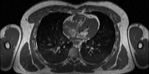

NMR

Pd                          / T2 \                         T1